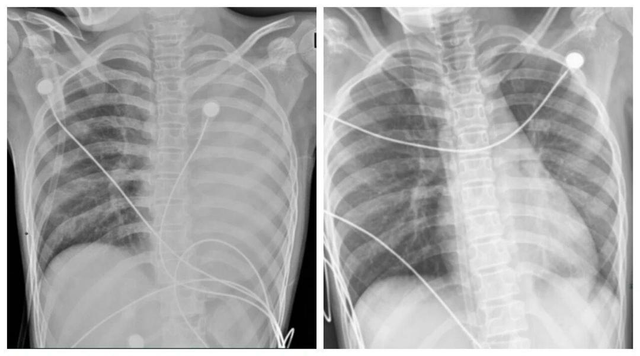

Những ngày gần đây, dư luận Trung Quốc đặc biệt chú ý tới một ca bệnh tại tỉnh Hà Nam, Trung Quốc: một bé trai 12 tuổi nhiễm cúm A chủng H3N2, chỉ sau 24 giờ hình ảnh phổi đã xuất hiện tình trạng viêm lan tỏa nghiêm trọng, còn gọi là “phổi trắng”. Trẻ rơi vào suy hô hấp nặng và chỉ được cứu sống nhờ hệ thống oxy hóa máu qua màng ngoài cơ thể (ECMO).

Về mặt y khoa, “phổi trắng” không phải phổi biến đổi màu sắc thật mà là hình ảnh X-quang hoặc CT cho thấy vùng viêm, thâm nhiễm chiếm trên 70% nhu mô phổi. Nếu được điều trị kịp thời bằng kháng virus, kháng sinh, rửa phế quản… phần lớn tổn thương có thể hồi phục.